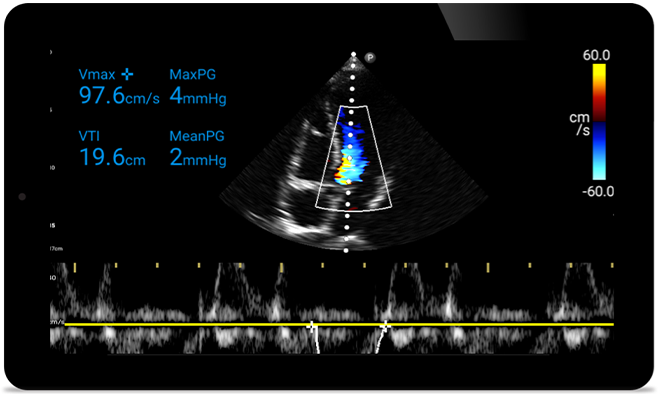

Actúe más rápido para proteger el corazón de sus pacientes

Cuando los segundos cuentan, el ultrasonido portátil puede marcar la diferencia. Lumify puede proporcionar las imágenes de alta definición que requiere cuando y donde las necesite.

Oportunidad de revertir potencialmente la miocardiopatía

Introducción a la ecocardiografía transtorácica